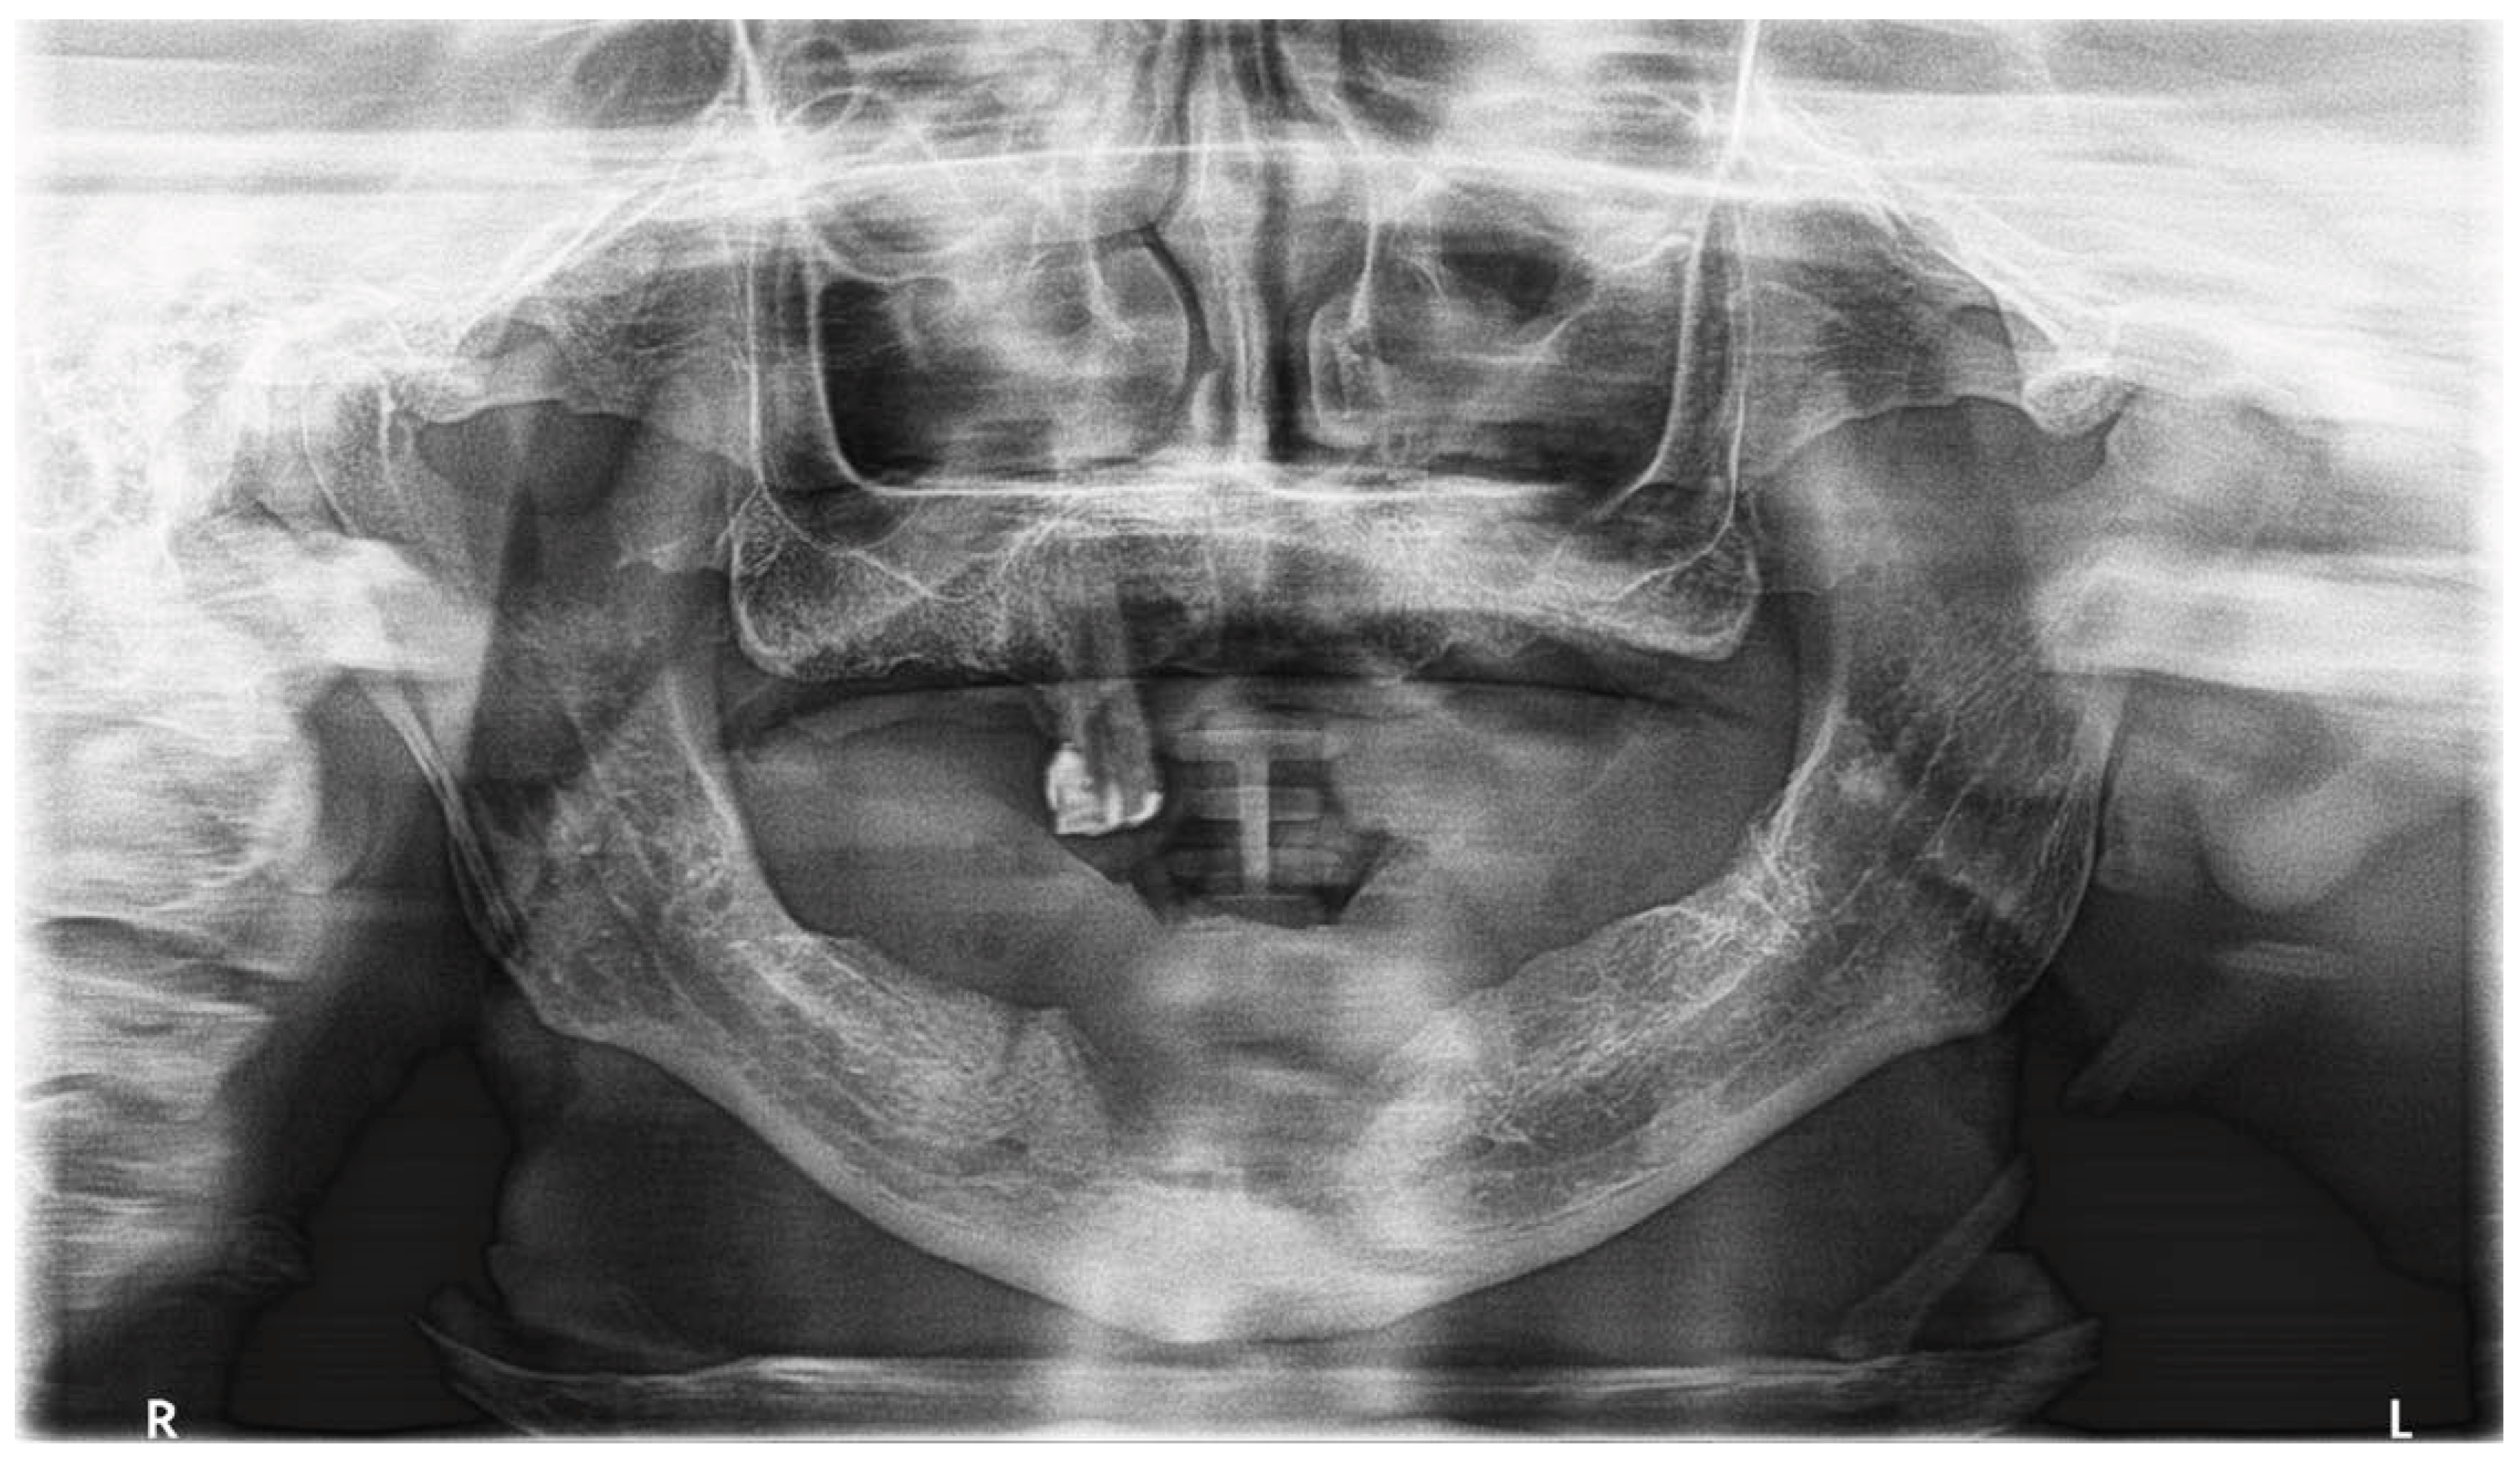

2.4. Diagnostic Assessment